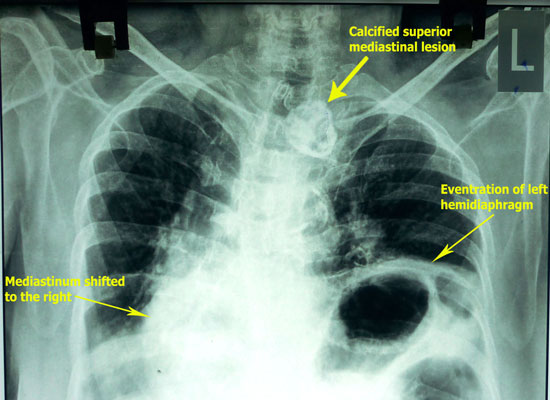

-A patient

presented with acute dyspnea.

-Patient was investigated and found to have eventration of diaphragm and

taken up for surgery for correction by cardiothoracic surgeon.

-Summary of radiological findings:

-Eventration of left hemidiaphragm with mediastinal & tracheal shift to

the right.

-Cardiomegaly with bilateral pleuarl effusion.

-Calcified lesion anterior and to left of trachea in the superior

mediastinum

(? calcified thyroid nodule, ? calcified lymph node)